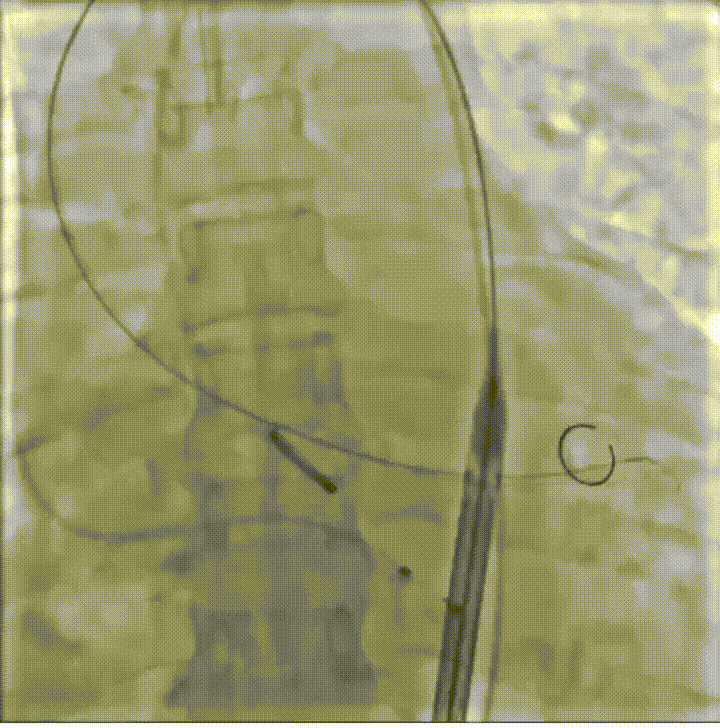

病例概览

患者病史 体检发现心脏瓣膜病半月余,平素无症状 ,有高血压病史。 后来院复查诊断为:主动脉瓣狭窄(重度)、先天性主动脉瓣二叶瓣畸形、心室肥厚、升主动脉扩张心功能 I 级(NYHA 分级)、高血压病 2 级(极高危)。 术前 CT:Type0型二叶瓣,瓣叶增厚,无钙化,类风湿性;瓣环径25.6mm,LVOT稍收窄,瓣环水平夹角66.6°,轻微横位心;左右冠开口高度可,瓣叶不长,无冠脉风险;心室收缩末内径约32mm,室壁增厚;外周入路无明显迂曲,无钙化、双侧内径可、双股中分叉,右侧为主入路能够支持20F大鞘通过。 造影角度及入路:LAO 6° CAU 13° 手术策略 采用右侧股动脉为主入路,左侧为辅助入路,常规穿刺。推荐使用20球囊预扩,预装TAV29瓣膜,初始定位对齐瓣环上0mm开始释放。 手术过程 20号球囊预扩无明显腰征 输送器过弓跨瓣顺滑 80%工作位观察 术后造影,瓣膜释放位置良好,无瓣周漏 术后超声:人工生物瓣释放后形态满意,瓣叶开放、关闭活动良好,无瓣周漏;跨瓣血流速度降至 2.5m/s,平均压力梯度6mmHg,符合手术预期。 Prostyle A®预装干瓣——“刚柔并济”助力临床最优化解决方案: 丝滑过弓能力:Prostyle A®短瓣架设计联合远端超滑亲水涂层,即使没有联合使用snare,都可以柔顺过弓,该例横位心的患者更好的展现了输送系统的柔顺性; 平衡的径向支撑力:该例患者Type0型二叶瓣,术后形态展开良好且无瓣周漏,在横位心等复杂情况下实现稳定锚定。 80%可回收设计:80%工作位观察,起搏时间更短,对患者损伤减少到最小,也利于术中精准调整瓣膜位置,保证术后效果。